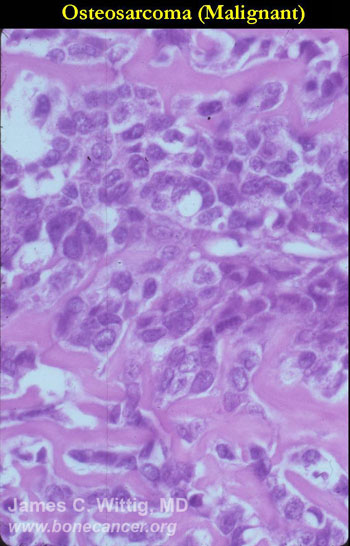

Microscopic Pathology: Conventional Osteosarcoma

- High grade anaplastic tumor

- Hypercellular, spindle cell tumor with extensive pleomorphism (cells are different sizes and shapes)

- Large nuclei and little cytoplasm (high nuclear to cytoplasmic ratio)

- Many mitotic figures and abnormal mitoses

- Bizarre appearing cells with hyperchromatic nuclei

- Osteoid production

- Osteoid is often laid down in lace-like pattern in between the malignant cells

- Osteoid stains pink to red with H&E stains

- No osteoblastic rimming (the cells do not line up on the surface of a trabecula of osteoid as in osteoblastoma or osteoid osteoma)

- Osteoid may or may not mineralize; degree of mineralization determines how visible it is on x-ray

- May have other elements such as cartilage, fibrous tissue, small round blue cells, giant cells and telangiectatic changes